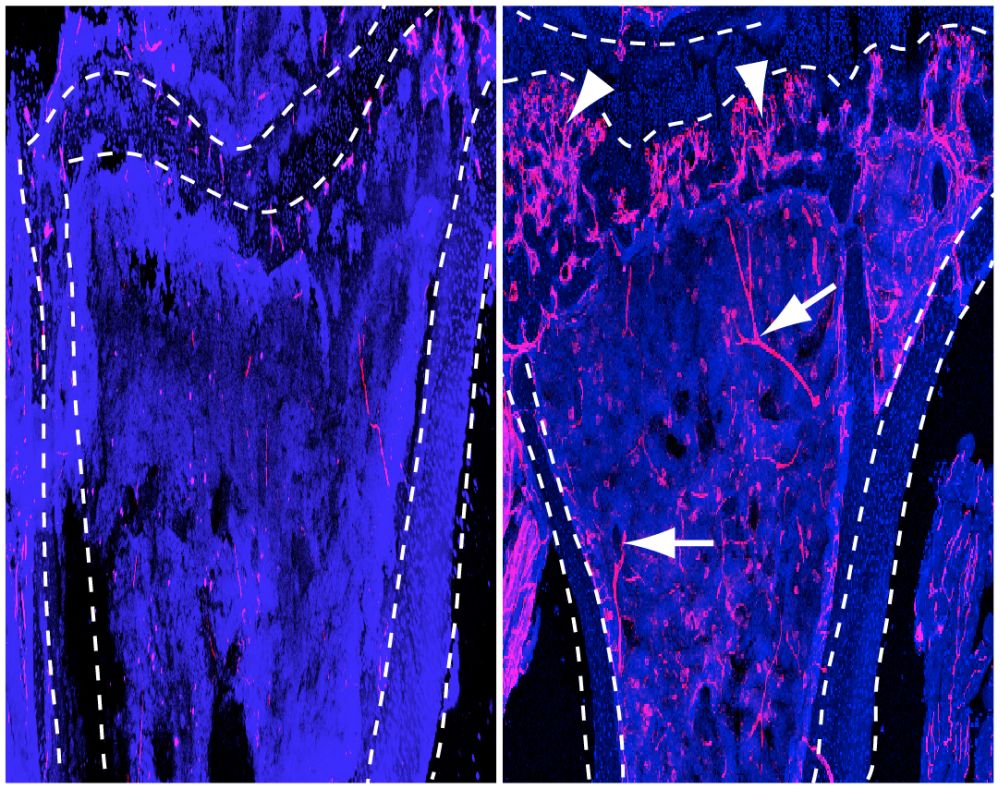

Dr. Rui Benedito, Postdoktorand in Adams Abteilung, konnte jetzt an Mausaugen zeigen, dass Blutgefäße durch Ausschalten des Notch-Signalwegs, eines steuernden Regelkreises, auch ohne die Aktivität von VEGF/VEGFR2 wachsen können. „In einem solchen Fall fördert dann ein weiterer, verwandter Rezeptor namens VEGFR3 die unkontrollierte Vermehrung von Blutgefäßen im Mausauge", erklärt Benedito. VEGFR3 wird durch das Fehlen von „Notch“ in den Gefäßen sehr stark hochgeregelt und ist dann auch ohne Signale aus der Gewebeumgebung aktiv.

Dr. Rui Benedito, Postdoktorand in Adams Abteilung, konnte jetzt an Mausaugen zeigen, dass Blutgefäße durch Ausschalten des Notch-Signalwegs, eines steuernden Regelkreises, auch ohne die Aktivität von VEGF/VEGFR2 wachsen können. „In einem solchen Fall fördert dann ein weiterer, verwandter Rezeptor namens VEGFR3 die unkontrollierte Vermehrung von Blutgefäßen im Mausauge", erklärt Benedito. VEGFR3 wird durch das Fehlen von „Notch“ in den Gefäßen sehr stark hochgeregelt und ist dann auch ohne Signale aus der Gewebeumgebung aktiv.